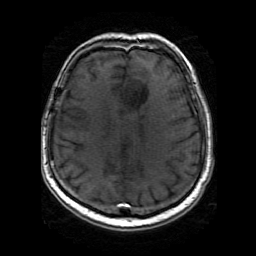

Sample case:

Figure 1 Original image (left) and same image after median

filtering with Window size= 3 (right)